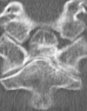

Eski Lomber Stabilizasyon Sistemi Altında Kırık (2)

Ağustos 2023